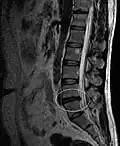

L'imagerie par résonance magnétique peut montrer la hernie, le canal vertébral, les nerfs, les tissus environnants. Les tissus mous sont les mieux analysés par cet examen qui est le plus performant pour le diagnostic de hernie discale. Les images pondérées en T2 montrent clairement la hernie.

IRM lombosacrée sagittale montrant une hernie discale de niveau L4-L5.

IRM lombaire sagittale montrant une hernie discale de niveau L4-L5.

IRM lombaire sagittale montrant une hernie discale de niveau L4-L5.- IRM lombaire sagittale montrant des protrusions discales.